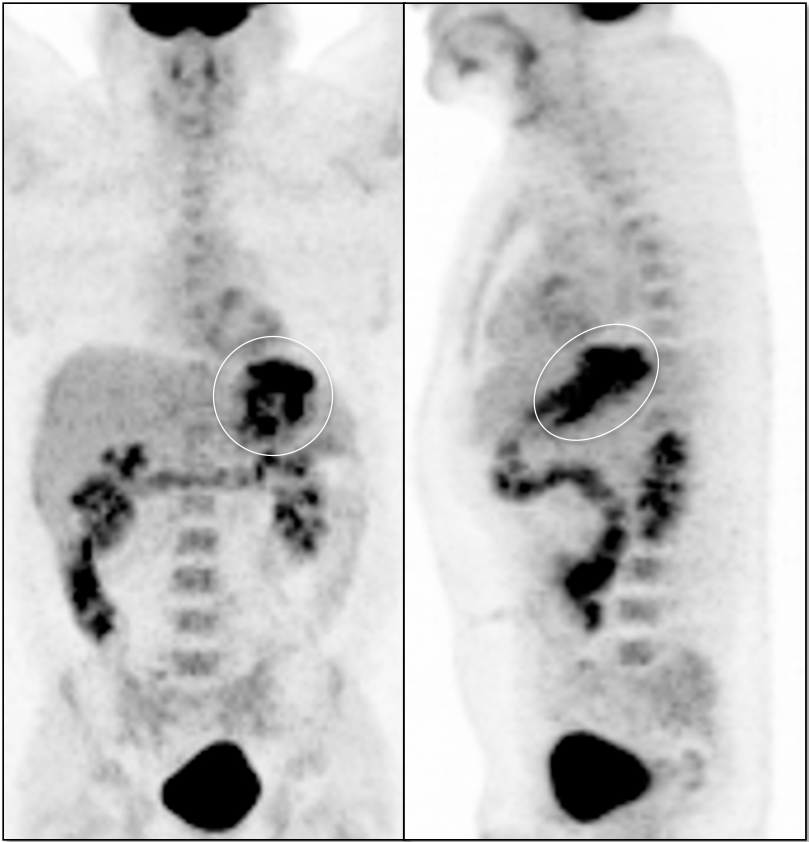

- Maximum Intensity Projection (MIP)

- Fusion of Images

3. Excellent Views: The MIP, Coronal & Sagittal Images

- 3-D Rotating MIP & Coronal “Quick MIP”

- Coronal PET

- Sagittal PET